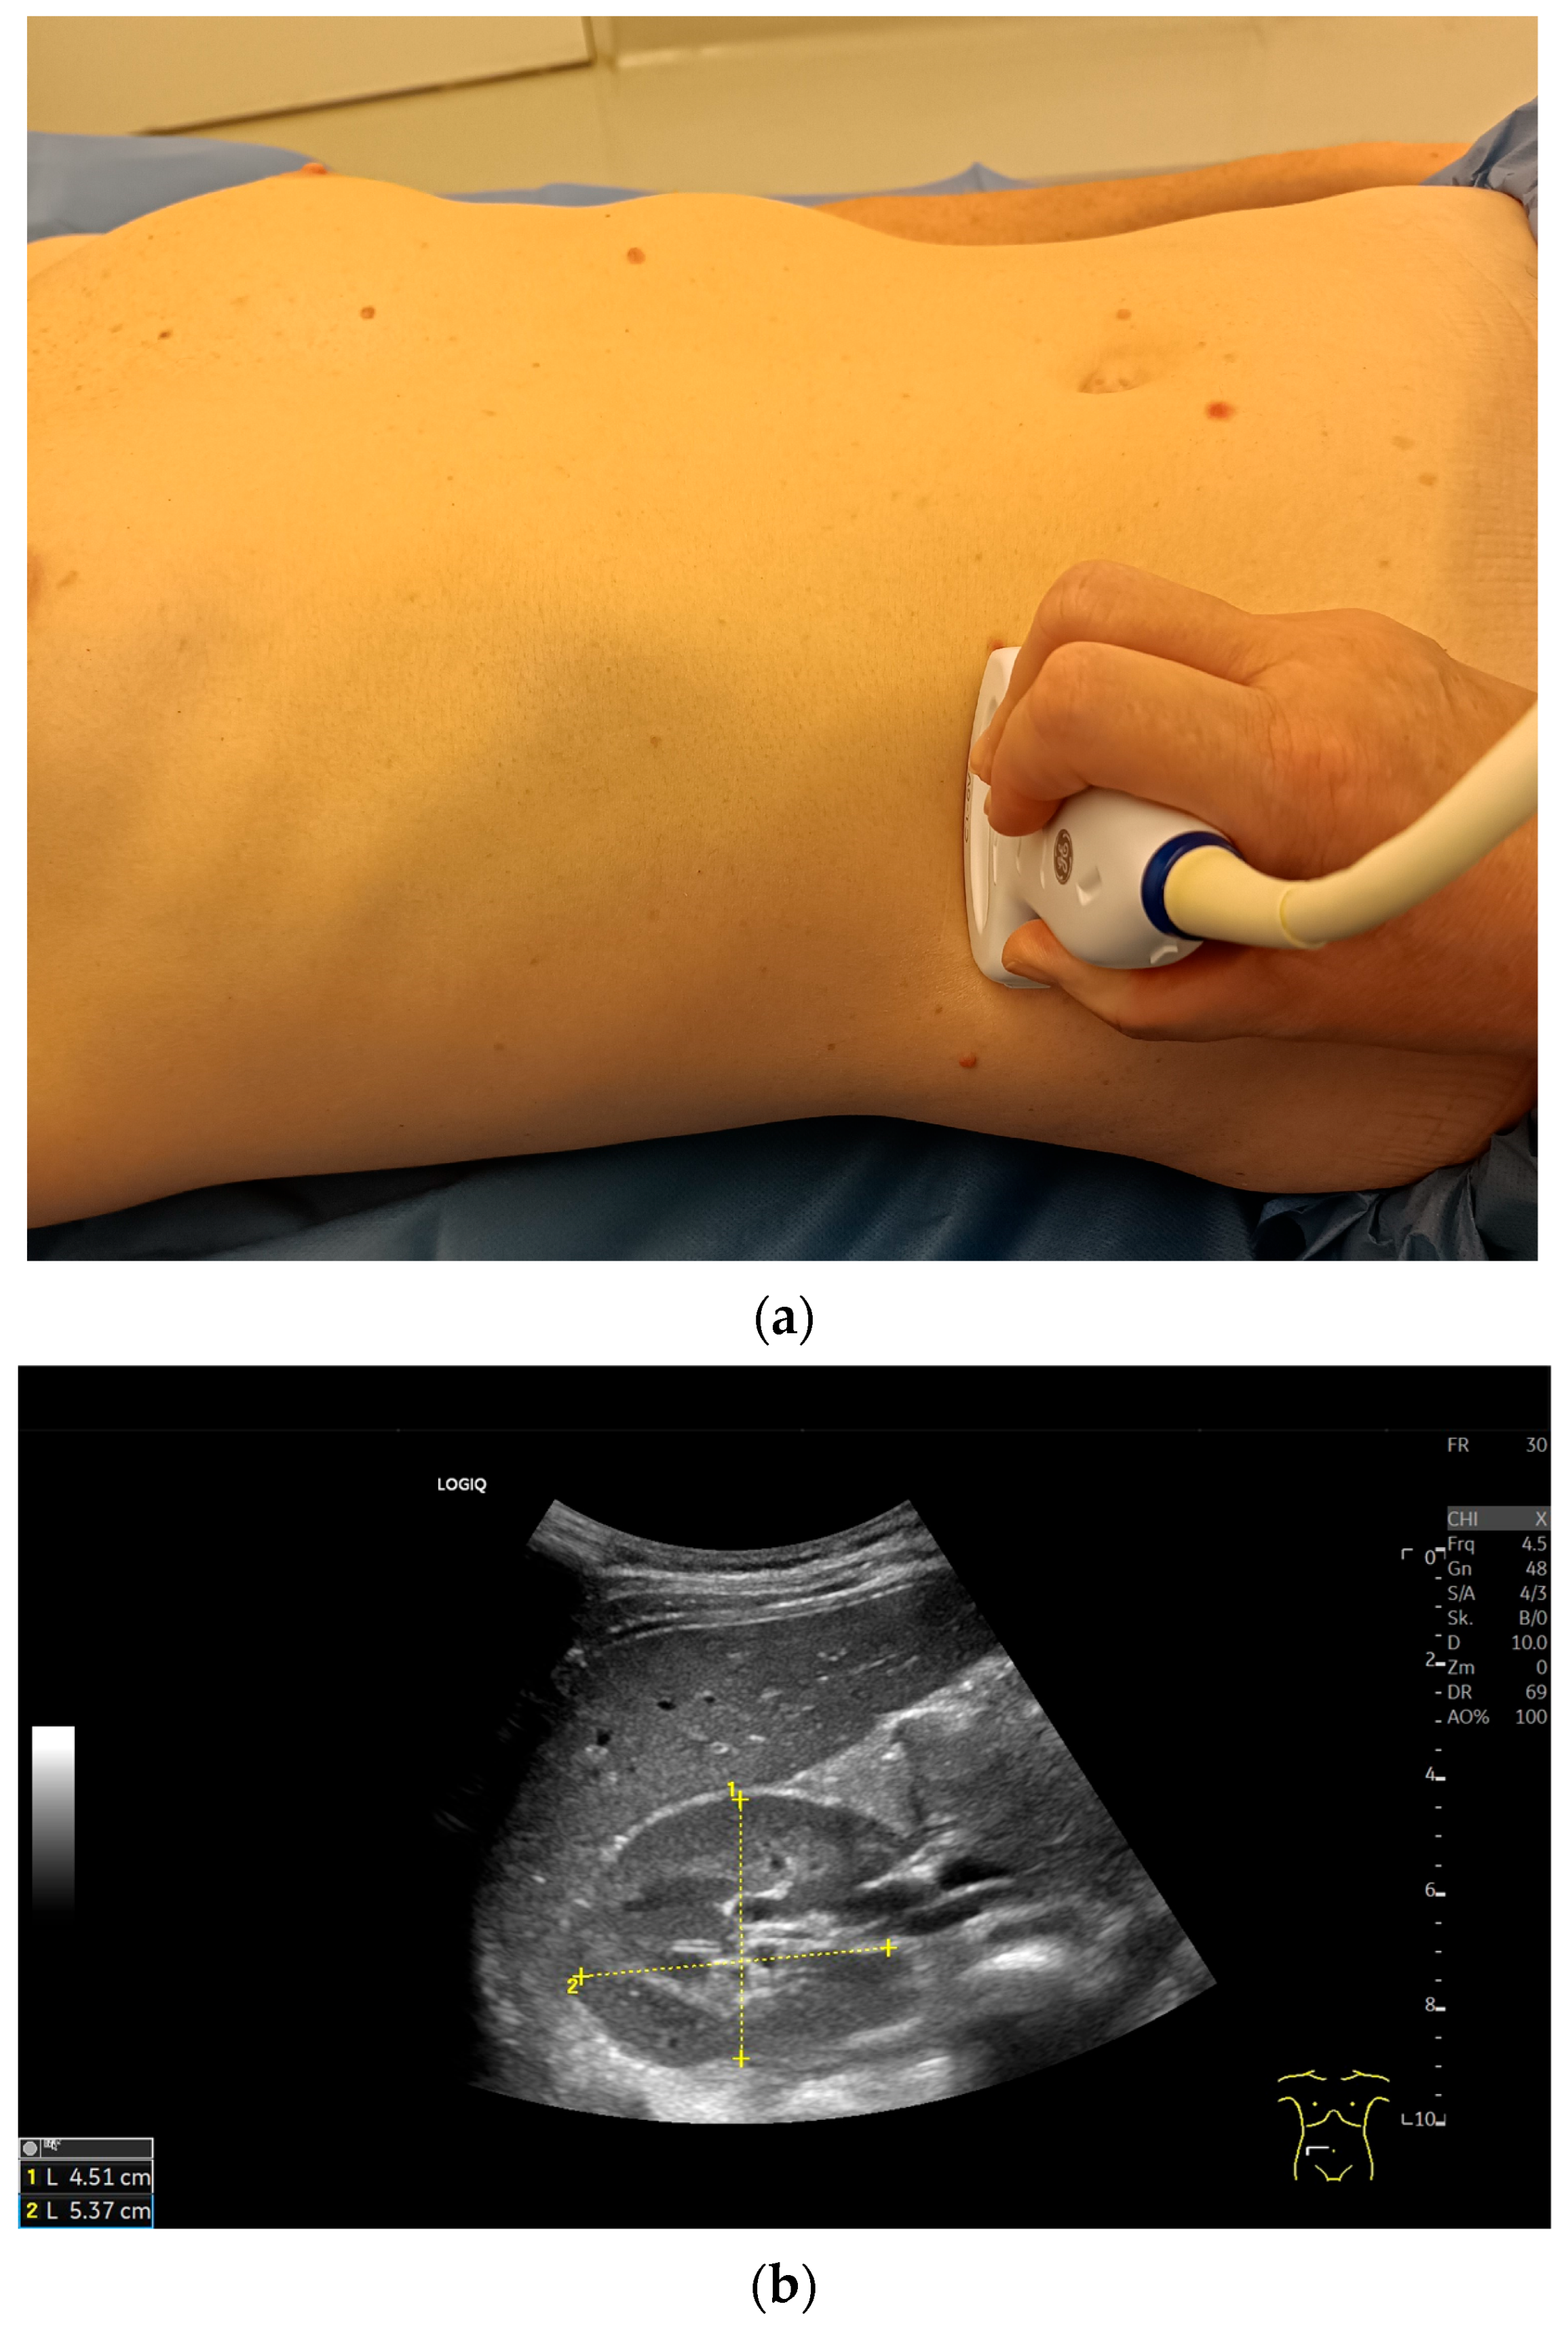

Imaging Techniques and Protocol

| Patient Position | Clinical Purpose |

|---|---|

| Supine | Opens up rib spaces to facilitate better visualization |

| Lateral decubitus | To reduce bowel gas interface |

| Oblique | In obese patients |

| Prone | Occasionally used for posterior access |

| Standing | In cases of clinically relevant suspicion of kidney descent when standing. |

| Length/maximum pole distance | Maximum length distance from the kidney contour at the upper pole to the contour at the lower pole. If the parenchymal margin at the upper and lower poles is of different thickness, the kidney is displayed tangentially. |